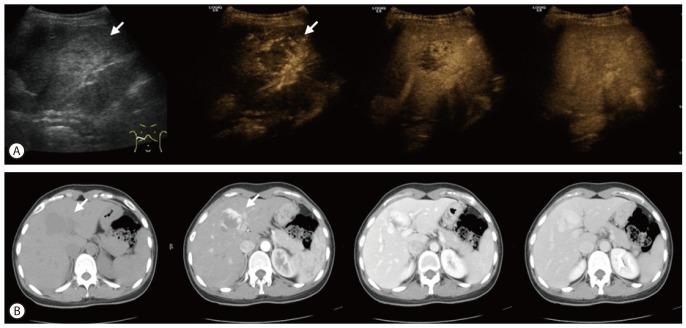

The application of ultrasound contrast agents (UCAs) is considered essential when evaluating focal liver lesions (FLLs) using ultrasonography (US). Microbubble UCAs are easy to use and robust; their use poses no risk of nephrotoxicity and requires no ionizing radiation. The unique features of contrast enhanced US (CEUS) are not only noninvasiveness but also real-time assessing of liver perfusion throughout the vascular phases. The later feature has led to dramatic improvement in the diagnostic accuracy of US for detection and characterization of FLLs as well as the guidance to therapeutic procedures and evaluation of response to treatment. This article describes the current consensus and guidelines for the use of UCAs for the FLLs that are commonly encountered in US. After a brief description of the bases of different CEUS techniques, contrast-enhancement patterns of different types of benign and malignant FLLs and other clinical applications are described and discussed on the basis of our experience and the literature data.

超声造影剂(UCAs)在超声检查评估局灶性肝脏病变(FLL)中被认为是必不可少的。微泡 UCAs 易于使用且稳定;其使用不会造成肾毒性风险,也无需电离辐射。对比增强超声(CEUS)的独特之处不仅在于非侵入性,还在于实时评估肝灌注的整个血管相。这一特性极大地提高了超声对 FLL 的检测和特征诊断的准确性,以及对治疗程序的指导和对治疗反应的评估。本文描述了超声常用的 UCA 在 FLL 中的应用的共识和指南。在简要描述了不同 CEUS 技术的基础上,根据我们的经验和文献数据,描述和讨论了不同类型的良性和恶性 FLL 以及其他临床应用的增强模式。